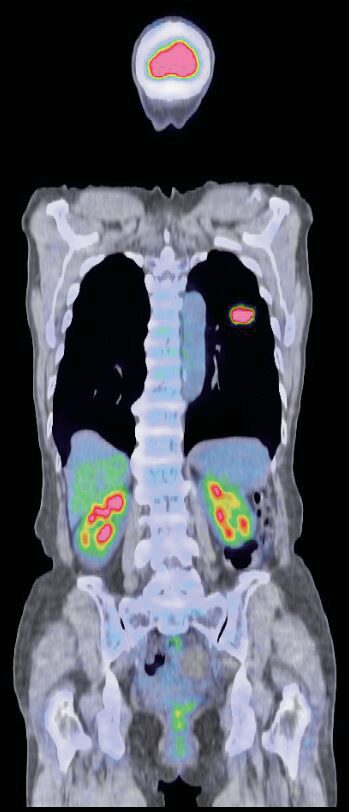

2026(令和8)年1月5日に、魚住クリニックから名称を変更した「あかりPET画像診断クリニック」。その名の通りPET(ペット)画像診断を専門とする医療機関だ。がんの早期発見につながるとして近年注目されているPET画像診断。もともとがん細胞は、健康な細胞と比べ、ブドウ糖を取り込みやすい性質がある。この性質に着目し、糖を含んだ薬剤を注射、全身のブドウ糖の代謝活動をPETカメラで画像化する。体内のブドウ糖の状態を見ることで、がん細胞の場所や性質、活動状況まで詳しく診断できる。

がんの大きさ・形を映し出すCTやMRIに対し、PET検査はがん細胞の活動性まで調べられるのが特長。良性腫瘍との鑑別や治療によって死滅しつつあるがん細胞、逆に今後大きくなりそうながん細胞などを見分けることができる。またCTとPETを組み合わせるとさらに精度は上がり、これまで見つけられなかったがんの発見や転移・再発の診断が可能になる。検査は問診後、薬剤を注射し、薬剤が浸透するまで1時間ほど安静待機、その後PETカメラで撮影する流れ。痛みはなく着衣のままで検査でき、一度の検査で全身の診断ができる。検査終了後はすぐ通常の生活に戻れるなど患者にとってメリットも多い。

PET診断を専門とする同クリニックは全国でも珍しく、県内で唯一(2026年1月現在)検査薬剤 を院内製造する設備を整えている。クリニック内のクリーンブースで薬剤を製造しているため、緊急の検査に対応できるほか、それぞれの患者の体重に合わせた薬剤を使うことで、より正確な画像診断につながる。 また、PET撮影機器は2台体 制。2026年のGW明けには「半導体PET」を新たに導入する。最新型の機器によって、さらに鮮明な 画像を得ることができる。患者は、9割が臨床施設からの 紹介。主にがん(早期胃がんを除く)の病期診断、転移・再発の診断において保険適応となる。 一方、自由診療の検診としてもPET画像診断が受けられる。全身をくまなくチェックすることから、自覚症状のない早期のがん発見につながるケースもあるという。